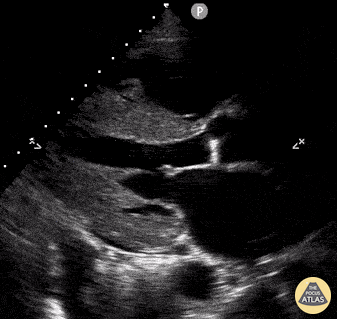

Parasternal long axis taken in a patient with clinical suspicion of cardiac amyloidosis. Maxime Gautier